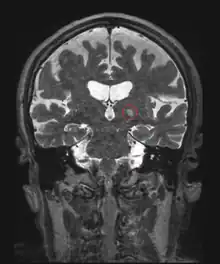

Frontal MRI four days after MRgFUS (MRI-guided high-intensity focused ultrasound): Left ventral intermediate nucleus (Vim) thalamotomy. 79-year-old man with essential tremor.

Additionally, MRI-guided high-intensity focused ultrasound is a nonsurgical treatment option for people with essential tremor who are medication refractory.[54][55] MRI-guided high-intensity focused ultrasound does not achieve healing, but can improve the quality of life by reducing the tremor manifestation.[55][56] While its long-term effects are not yet established, the improvement in tremor score from baseline was durable at 1 year and 2 years following the treatment.[57] To date, reported adverse events and side effects have been mild to moderate. Possible adverse events include gait difficulties, balance disturbances, paresthesias, headache, skin burns with ulcerations, skin retraction, scars, and blood clots.[54][55][58] This procedure is contraindicated in pregnant women, persons who have non-MRI compatible implanted metallic devices, allergy to MR contrast agents, cerebrovascular disease, abnormal bleeding, hemorrhage and/or blood clotting disorders, advanced kidney disease or on dialysis, heart conditions, severe hypertension, and ethanol or substance abuse, among others.[55] The US Food and Drug Administration (FDA) approved Insightec's Exablate Neuro system to treat essential tremor in 2016.[55]